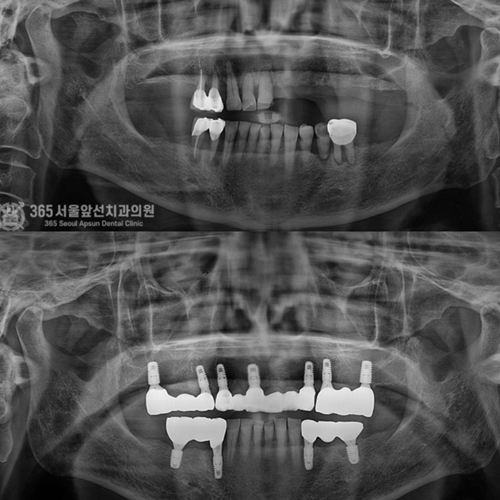

발치와 임플란트 시술이 단 하루만에!

원데이 임플란트

단 한번의 수술만으로 발치와 동시에

즉시 임플란트를 식립하여 불편감을 줄이고 치료기간을 단축할 수 있습니다.

평균 악당 30분의 빠른 식립시간, 치료 케이스 다수 보유

전체 임플란트

상·하악 전체 치아를 대체하는 임플란트로 최소한의 식립을 통해

자연치아와 비슷한 기능을 수행할 수 있도록 합니다.